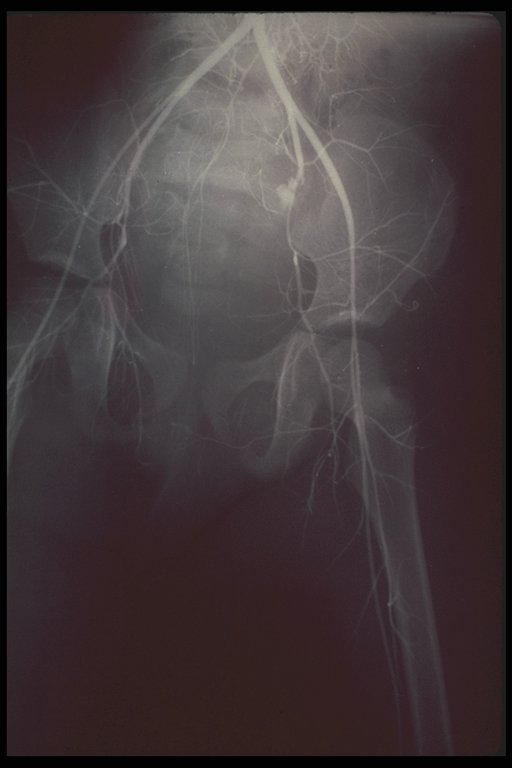

After blocking the point of bleeding with gelfoam. The X-ray showed no further leakage. This boy was saved by non-operative management